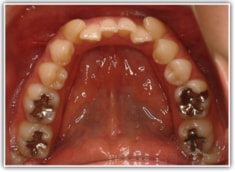

セファロ分析結果:上顎の劣成長と下顎の過成長が認められる値が出ています。重度の叢生といえます。

修復歯、補綴歯もあります。下顎8番が水平埋伏しています。